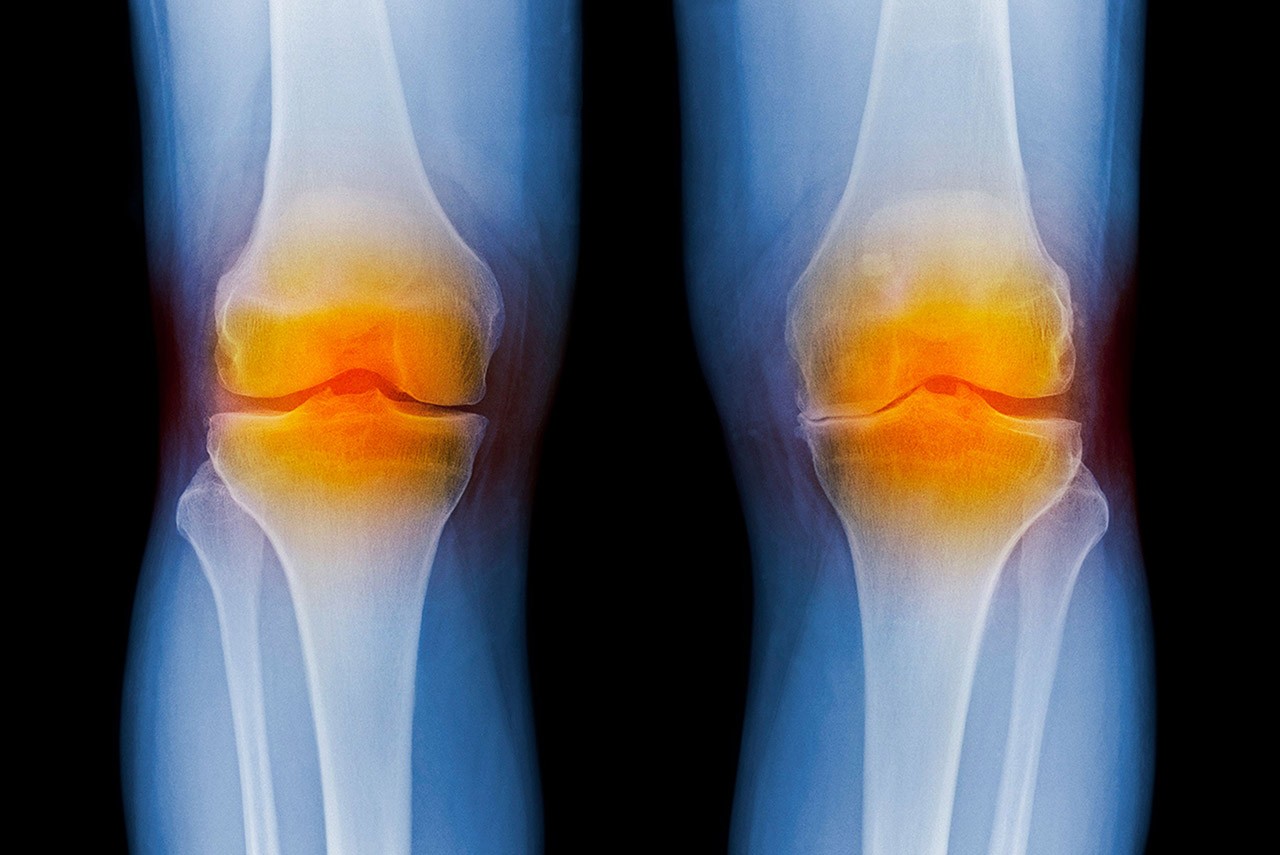

Engineering dean partners with fellow researchers to develop breakthrough therapy for osteoarthritis